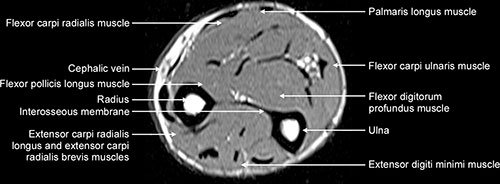

32+ Forearm Muscles Anatomy Mri. All superficial muscles are arises from the medial epicondyle of humerus but they are inserted into the different part except. Forearm fractures anatomy and assessment orthopaedicprinciples com.

Fortunately, there's some patterns that can make the forearm a little bit easier.

3d anatomy tutorial on the muscles of the flexor compartment of the forearm. The brachioradialis is a muscle of the forearm that flexes the forearm at the elbow. Mri of the upper limb. Magnetic resonance imaging (mri) utilizes magnet and radio waves to produce diagnostic images that allow a doctor to visualize the hips.